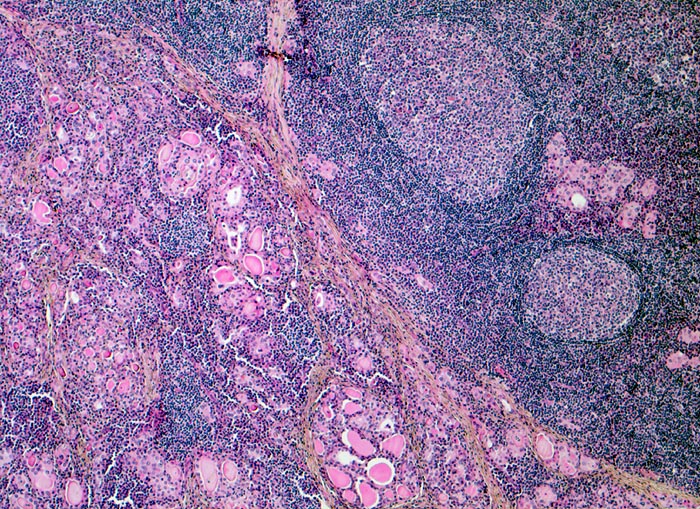

Die zytologische Diagnose einer Hashimoto Thyreoiditis gelingt meist eindeutig. Der Autoimmunprozess ist mit einer chronischen Entzündung verbunden, die zu einer Zerstörung der Schilddrüsenfollikel führt. Das Entzündungsinfiltrat besteht aus Lymphozyten, Plasmazellen, lymphohistiozytären Aggregaten, Sternhimmelmakrophagen und Riesenzellen. Im Hintergrund sind lymphoglanduläre Körperchen zu sehen. Schaumzellen und Makrophagen sind gelegentlich beigemischt. Als Folge der Gewebsdestruktion ist das follikuläre Epithel degeneriert (Kernpyknosen, vakuolisiertes Zytoplasma) oder zeigt eine onkozytäre Metaplasie teilweise mit Atypie. Die Diagnose der Hashimoto Thyreoiditis basiert auf dem Nachweis von chronischer Entzündung und Onkozyten.